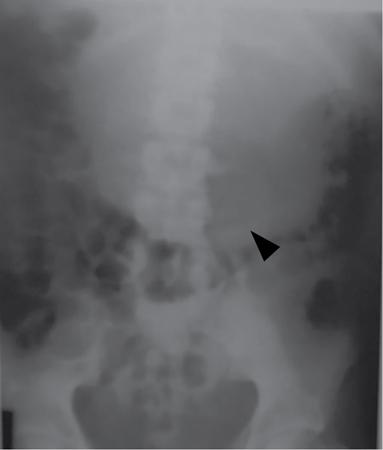

UNDERSTANDING THE ADULT ABDOMINAL RADIOGRAPH: TECHNIQUES AND INTERPRETATION Tanvi Modi Radiography of the abdomen is a common practice for the evaluation of abdominal organs. The anatomy and pathology of digestive, hepatobiliary and genitourinary systems can be assessed using radiographs, either as a stand-alone practice or as a primary imaging modality followed by contrast studies, ultrasound or cross-sectional imaging. In addition, abnormalities of the musculoskeletal or integumentary system can also be deduced on the basis of abdominal radiographs. This chapter intends to give an overview on the techniques and positioning in abdominal radiography as well as interpretation of normal and abnormal features. While superior imaging modalities such as ultrasound, computed tomography (CT), magnetic resonance imaging, capsule endoscopy and the likes have taken over abdominal imaging by and large, radiography still holds a pivotal role in certain situations and conditions, such as: The standard abdominal radiograph is taken in supine position and anteroposterior projection. This is also popularly known as the KUB (kidneys-ureters-bladder) radiograph. Previously, supine as well as erect radiographs were performed in all patients; however, this is not commonly done due to high-radiation dose. For all indications of abdominal radiography, including acute abdomen, supine radiographs are sufficient in terms of radiographic diagnosis, with the exception of perforation for which an erect chest or lateral decubitus radiograph can be performed if there is clinical suspicion. Patient should lie supine on the imaging table with median sagittal plane at right angles to the table and coincident with the midline of the table (Fig. 7.1.1.1). The body is divided into equal right and left halves by the median sagittal which passes through the sagittal suture of the skull. Pelvis should be adjusted so that the anterior superior iliac spines are equidistant from the table top. Gonadal shields, in the case of male patients, should be placed with the upper edge of the shield at the level of pubic symphysis. Although rarely used for female patients, these should be positioned between the anterior superior iliac spines and the pubic symphysis. The centre point of the image receptor should be approximately located at a point 1 cm below the line joining the iliac crests. The X-ray beam should be in a vertical direction, perpendicular to the table top and image receptor at the centre point. Collimation should be such that the soft tissue and subcutaneous region along lateral aspects of the abdominal cavity should be covered within the image. Also, the superior extent involving diaphragm and inferior extent involving the inferior pubic rami is important to look for any lower chest pathologies or any inguinal hernia. 35 × 43 cm (14 × 17 inches) in portrait orientation. On an average, abdominal radiograph exposes a patient to a dose of approximately 1.5 mSv, which is equivalent to 75 chest radiographs or 1/6th dose of a standard CT of the abdomen. The entrance skin dose is approximated to be 4 mGy. At such an effective dose, the additional lifetime risk of fatal cancer is 1 in 30,000. The exposure time is kept short. Patient is asked to exhale completely and hold their breath, with exposure taken at this point of full expiration to ensure imaging of abdominal organs in their natural positions. Modifications of this technique can be made depending on patient habitus and clinical condition. Kilovoltage peak (kVp) should be set to allow adequate visualization of abdominal soft tissue structures as well as semiopaque renal and biliary calculi. Average kVp is set at 70–85 kV. 102 cm (40 inches) Grids are commonly used to reduce scatter radiation. Placement of side marker on the image receptor at the time of radiographic exposure is essential. Bowel pattern depiction should be such that there is minimal lack of sharpness. Standard guidelines for abdominal radiography dictate that the radiograph should extend from the diaphragm up to the level of inferior pubic rami and must include the lateral abdominal wall musculature. The abdomen is divided into four quadrants on the basis of two perpendicular lines (Fig. 7.1.1.7). The vertical line passes through the mid sagittal plane and crosses the umbilicus and symphysis pubis. The horizontal line is a transverse line across the umbilicus at 90 degrees to the vertical line and is situated at the level of L4–L5 intervertebral disc. The quadrants are as follows: Another division system is dividing the abdominopelvic cavity into nine regions using two vertical and two horizontal planes (Fig. 7.1.1.8). The vertical planes, also known as the right and left lateral planes, are parallel to the midsagittal plane between midline and anterosuperior iliac spines on either side. Of the two horizontal planes, the upper transpyloric plane is at the level of lower border of L1 and the lower transtubercular plane is at the level of L5. The nine regions are: On a standard radiograph, the exposure should be such that the stomach, bowel loops, outlines of liver, spleen, kidneys, psoas muscles should be well identified. Also, lumbar transverse processes should be seen. Arch of the pubic symphysis should be visible to evaluate bladder region. A well-centred film without rotation will demonstrate bilaterally symmetrical lower ribs, iliac wings, ischial spines and obturator foramina. Different structures seen on an abdominal radiograph can be classified into five basic densities: Identification of different structures depends on the relative degree of contrast between their densities. The demarcation is clearer in chest and is diminished in abdomen due to relative similar soft tissue density of various structures. On a normal radiograph, relatively large amounts of gas in stomach and colon with minimal small bowel gas can be seen. Further, colonic gas can vary from negligible to extensive, mimicking obstruction pattern; however, usually the gas is enough to delineate colonic haustral pattern. Faecal matter gives a mottled appearance to colonic gas. Short-air fluid levels on an erect radiograph may be seen even in normal cases. The normal appearance of small bowel loops on an abdominal radiograph follows the rule of threes: Stomach is seen in the left upper quadrant and is visualized when distended with air. It is commonly seen extending from T11 to L2 level. Common feature identifying the stomach is the fundal gas which is usually seen as an air fluid level within the gastric lumen. Small bowel loops are distributed to the centre of the abdominal cavity and large bowel loops are peripheral. Duodenum is predominantly situated in right upper quadrant. It extends to left upper quadrant in the region of duodenojejunal flexure. Jejunum occupies the left upper and lower quadrants and is easily identified due to the presence of thick, numerous, closely spaced valvulae conniventes (Fig. 7.1.1.9A). The ileum occupies both lower quadrants and extends into right upper quadrant. Ileum has few and less prominent valvulae as compared to jejunum (Fig. 7.1.1.9B). Ascending and descending colon are retroperitoneal and have relatively fixed positions along lateral aspect of the abdominal cavity on either side. Transverse and sigmoid colon, on the other hand, may have a variable position due to their mobility along mesocolon and redundant pattern. These can be identified with confidence on account of haustrations and faecal matter (Fig. 7.1.1.10). Haustrations are usually well seen in ascending and transverse colon and poorly delineated beyond splenic flexure. Caecum is in the right lower quadrant, though it may be mobile or pulled up. Rectal gas is usually seen in the midline at the level of pelvis and its presence rules out large bowel obstruction. All these positions may vary due to anatomical conditions such as malrotation or pathological conditions, for example volvulus. Liver, spleen and renal outlines cannot be completely traced with precision due to the overlap by bowel loops. On a frontal projection, the liver appears as a triangular structure occupying right and left hypochondrium and epigastric region. Occasionally, the right lobe may be seen extending lower than the right renal shadow. This is a normal variant known as Reidel’s lobe. Gall bladder is situated in the posterior and inferior region of the liver and any pathology of the gall bladder should be looked for in this region. On a lateral radiograph, the gall bladder is anterior to the midcoronal plane. This helps in distinguishing gall bladder calculi from renal calculi, which will be more posteriorly situated. Spleen is seen in left upper quadrant/left hypochondrium, flushed to left lower ribs and left hemidiaphragm. Pancreas is present in the epigastric region (right and left upper quadrants) and is usually not identified in the absence of a pathology. The kidneys are bean-shaped retroperitoneal organs which are seen on either side of the vertebral column and lateral to psoas muscles. Due to the presence of liver on the right side, this kidney is slightly lower in position as compared to its contralateral counterpart. The visualization of kidneys on radiographs is facilitated by the surrounding fatty capsule. Kidneys lie between T11–12 and L2 level, with left kidney 1 cm higher than the right. Psoas muscle shadow can be normally seen along lateral aspect of lumbar spine bilaterally and is mildly concave (Fig. 7.1.1.11). Abdominal wall muscles are not routinely assessed on radiography; however, inclusion of lateral abdominal wall (muscles as well as subcutaneous plane) is a must while performing radiography. The flank stripe or the properitoneal fat stripe is a fat density linear concavity seen along lateral abdominal wall (Fig. 7.1.1.11). It is bound by the paracolic gutters and air-filled ascending and descending colon. All the solid organs in the abdomen are identified due to the fat density outlining them. Distortion of these fat lines helps in identifying organomegaly or focal mass lesions. The dome of urinary bladder is outlined by fat, which aids in differentiating its density from other soft tissue structures of the pelvis. Not all calcifications seen on abdominal radiograph are abnormal. Some may depict age-related changes such as vascular calcifications involving abdominal aorta, pelvic vessels, splenic artery in the region of left upper quadrant. Within the pelvis, phleboliths may be seen and mistaken for urinary calculi. Assessment of lumbosacral spine, iliac bones and femoral heads can be made on the basis of plain radiography. Degenerative changes may be commonly seen. Lower ribs can also be evaluated for pathologies. Dilated small bowel loops with rounded soft tissue density in midline over umbilical region suggests obstruction secondary to umbilical hernia. Pneumoperitoneum must be looked for in all cases of acute abdomen. While erect chest and left lateral decubitus radiographs can detect even 1 mL of free air, there are multiple signs on supine radiograph to suggest this diagnosis, for example Rigler’s sign, falciform ligament sign, football sign (Figs. 7.1.1.24 and 7.1.1.25). Retroperitoneal perforation may demonstrate air outlining psoas muscles and retroperitoneal organs. Small amount of free air may persist in the abdominal cavity up to 3 weeks after surgery, although it usually resolves within a week. Clinical history is important in such cases. Air foci within the bowel wall may represent bowel ischaemia/strangulation. Linear gas patterns in right hypochondrium may be due to two causes, that is pneumobilia and pneumoporta. The former can be seen normally postbiliary surgery, sphincterotomy, ERCP or in the case of abnormal fistulous communication between bowel and biliary tree (Fig. 7.1.1.26A). Pneumoporta (Fig. 7.1.1.26B) is a red flag and warrants further investigation to look for conditions such as mesenteric ischaemia and toxic megacolon. Pneumobilia is more centrally located whereas air shadows in pneumoporta are seen reaching up to periphery of liver. Air foci over renal shadows (Fig. 7.1.1.27), gall bladder or pancreas, in the absence of recent procedural history, suggest fulminant infection and mandate urgent intervention. Central midline calcific foci between T9 and T12 vertebrae can be attributed to calcific pancreatitis (Fig. 7.1.1.28). In the left upper quadrant, areas of calcification seen involving a shrunken spleen may be seen in autosplenectomy. In right upper quadrant, calcified gall stones may be seen. These tend to be small, multiple, uniformly circumscribed and ring-like in appearance with central translucency (Fig. 7.1.1.29A). Mercedes Benz sign, a triradiate pattern of gas lucency, is associated with gallstones. In contrast, renal calculi are more commonly solitary, irregular, of homogenous density, conform to renal calyceal or pelvic outline (Fig. 7.1.1.29B) and are sometimes of staghorn configuration. On lateral view, the gall stones are more anteriorly located as compared to renal calculi, which may be partly superimposed on lumbar vertebrae. Ureteric calculi tend to overlap bony structures such as lumbar transverse processes (Fig. 7.1.1.29B) or sacroiliac joints. Extensive or patchy, curvilinear calcification of gall bladder wall is known as porcelain gall bladder which is often associated with malignant transformation. Calcification involving adrenal glands may be secondary to infection or haematoma, or a congenital condition known as Wolman’s disease where there is bilateral involvement. Discontinuous discrete midline tram track calcification in the abdomen may indicate atherosclerotic changes in abdominal aorta and branch vessels. However, when the calcification is in a globular pattern and seen below the level of L2 vertebra, aortic aneurysm should be suspected (Fig. 7.1.1.30). Appendicoliths, though not commonly seen, may sometimes be detected in right iliac region. Pelvic calcifications: vesical calculi, distal ureteric or vesicoureteric junction calculi, calcified fibroids, ovarian dermoid with tooth-like calcifications (Fig. 7.1.1.31) may be the cause of abdominal pain and should be diligently looked for. Vesical calculi are usually more large and central in location whereas calcification due to fibroids may be more lateral. Schistosomiasis is another cause of bladder wall calcification, as is calcification of bladder tumours. Phleboliths tend to be bilaterally symmetrical, with a lucent centre unlike ureteric calculi. While it is believed that phleboliths are located below the level of ischial spines and ureteric calculi above, this is not always true and should be confirmed with CT. Fluid may collect adjacent to properitoneal fat line, forming a linear soft tissue density separating the fat line from the ascending or descending colon. Hellmer’s sign demonstrates medial displacement of lateral edge of liver (hepatic angle), due to fluid collection or ascites. Gross ascites may appear as generalized abdominal haziness or diffuse increased density of pelvis. Abscesses can involve any solid organ and in such cases may be difficult to demonstrate on plain radiography alone. Enlargement of organ or faint gas densities within can be suggestive of the same. In the case of peritoneal abscess, mottled density due to air, fluid and necrotic contents point towards this diagnosis, especially in right iliac fossa in association with appendicitis. Retroperitoneal abscess, similar to any retroperitoneal mass, may cause displacement of retroperitoneal structures (Fig. 7.1.1.32). Subdiaphragmatic abscesses may show concomitant ipsilateral pleural effusion (Fig. 7.1.1.33). These should be differentiated from Chilaiditi syndrome. Fluid and soft tissue lesions present with the same density on radiographs. While it is difficult to characterize the lesion and organ of origin, clues for the same can be provided by organomegaly (Fig. 7.1.1.34), distortion of fat surrounding solid organs, displacement of bowel loops or solid organs. For example, a retroperitoneal lesion may cause anterior or inferior displacement of kidney, a pelvic mass may cause upward displacement of small bowel loops. Different densities such as fat or calcification may help in identifying organ of origin (e.g. fat and tooth densities seen in ovarian dermoid). Convexity of margins of psoas muscle on an abdominal radiograph can be due to haematoma, abscess or intramuscular tumour. Radiographs are performed for the initial diagnosis of foreign body in the abdomen including type, number of foreign bodies, location, size and shape (Fig. 7.1.1.35). Radiolucent foreign bodies such as wood, plastic, chicken bones will not be easily identified on radiography. Low kVp (65–70 kVp) can increase contrast and help identify these objects. In addition to an abdominal radiograph, chest radiography is also performed to exclude aspiration or oesophageal location of foreign body. Ingested or introduced foreign bodies may cause complications such as obstruction, perforation, fistula formation and sepsis. Hence, once their presence is confirmed, follow up radiography must be performed until they are eliminated. One must look for fractures/dislocation injuries involving the vertebrae or pelvic bones, especially after history of trauma. Lucent expansile lesions or sclerotic bony deposits which represent neoplasms, absent pedicle sign in cases of metastasis, metabolic bony changes such as rugger jersey appearance, Paget’s disease, arthropathies such as ankylosing spondylitis with bamboo spine appearance and sacroiliitis (Fig. 7.1.1.36) are some of the conditions which may be diagnosed based on an abdominal radiograph. Overlap of bowel loops over iliac blades may lead to a misdiagnosis of lucent lesions and should be evaluated with caution. Basal pneumonia may be the cause of acute abdominal pain and should be looked for in abdominal radiography. Similarly, pleural effusion, pericardial effusion, calcified pleural plaques, achalasia, interstitial fibrosis are few other findings that can be seen in lower chest on an abdominal radiograph. Basilar atelectasis can give a deceptive appearance of pneumoperitoneum (Fig. 7.1.1.37). Surgical clips, commonly in right hypochondrium after cholecystectomy, drainage tubes, ventriculoperitoneal shunts, femoral line catheters, IVC filters, stents (vascular, renal, biliary) (Fig. 7.1.1.38), stoma bags, contraceptive devices are some structures that may be seen in an abdominal radiograph. Correct knowledge of patient history and normal locations of these structures prevents misdiagnosis. Certain artefacts may be projected upon the radiograph due to surface structures such as trouser buttons, body piercing, sequins over clothing and should not be considered as a pathology. Multiple skin surface nodules in cases of neurofibromatosis, soft tissue focal swellings, such as abscesses, lipomas, haematomas, desmoid tumours and malignant lesions may be incidentally seen on radiography. These can be further evaluated using ultrasound or CT. Subcutaneous emphysema is another finding that may be seen in lower abdominal wall secondary to retroperitoneal perforation or diffusely along abdominal wall in the case of bowel perforation (Fig. 7.1.1.39). Foreign bodies such as bullets and pins may be seen lodged in abdominal wall. A systematic approach to abdominal radiographs is important for accurate diagnosis as follows: Despite the development of newer techniques for imaging of the abdomen, plain radiography still holds an important place in the initial assessment of acute abdomen. Positive and negative findings on an abdominal radiograph can direct further investigation. Ideal positioning, recognition of normal appearances and keen scrutiny for pathologies is a sine qua non for radiologists reading a plain film of the abdomen. OESOPHAGOGRAM Padma V. Badhe, Vikram Reddy, Sultan Moinuddin Shaukatali, Zillani Alam, Ravi Varma, Abhishek Bairy, Dasari Ravikiran, Revati Tekwani, Soniya Patankar, Megha Nair, Gautham Shankar Oesophagogram is the process of obtaining radiological images and simultaneous motion recording to evaluate function and disorders of pharynx, oesophagus and proximal stomach. Oesophagogram is usually done primarily to evaluate dysphagia. Some of the common indications are oesophageal motility disorders, strictures, gastro-oesophageal reflux disease (GERD) and suspected masses. It can also be used to detect uncommon anomalies like vascular rings/slings and aberrant anatomy. It also helps to evaluate further in cases where there is inability to pass upper GI scope. Double-contrast oesophagogram is mainly indicated in early mucosal disease like erosion, polyp, infection and tumours. If a motility disorder is suspected, dynamic technique (e.g. videofluoroscopy) is used for dysphagia or aspirations in cases of stroke, neuromuscular disorders, post head and neck surgery or radiation. Barium oesophagogram is contraindicated in suspected cases of perforation and tracheoesophageal fistula, aspiration, rarely if there is hypersensitivity to barium suspensions. It is also contraindicated in suspected oesophageal perforation where a water-soluble contrast agent is more suitable. However, ionic water-soluble contrast agent is better avoided in cases of aspiration or fistula with airway. The contrast examination of the pharynx is dangerous in cases of acute epiglottitis and must be ruled out on plain radiograph. An 80% w/v barium suspension is used in full column views. However, 200%–250% w/v barium suspensions is usually required for mucosal relief films. The barium sulphate mixture is fed to the patient either by spoon, by glass, or through a drinking straw, depending on its consistency. In videofluoroscopy, the pharyngeal phase of swallowing is usually safer with barium pudding than with thick barium and safer with thick barium than with thin barium. However, if the major abnormality is poor pharyngeal contraction leading to stasis in the piriform sinus (and epiglottic tilt is normal), a thin liquid is safer. Epiglottic motility is better assessed with thin barium because thick barium often obscures the epiglottic tip. Fluoroscopic equipment capable of cine fluoroscopy and capability for rapid sequence spot images (high frame rate) is needed for this examination, Barium suspension, straw, glass, Lead apron and radiation protective equipment. The patients are instructed to fast after midnight before the day of the examination. The pharynx should be made as dry as possible during the examination as high-density barium adheres to dry pharyngeal mucosa. Activities like smoking, chewing gum and lozenges must be abstained before the procedure as they impair barium coating by increasing the salivary secretion. Regular oral medications must be taken with sips of water; however, insulin must be skipped on the morning of examination. The major principles of a good oesophagogram includes mucosal coating, distension and projection. A routine oesophagogram consists of screening of the oral, pharyngeal and oesophageal phases of swallowing, single and double-contrast examination of pharynx, single contrast, double-contrast and mucosal relief views of the oesophagus. In cases of dysphagia, the examination is tailored depending on whether the symptoms are either pharyngeal or oesophageal and initial fluoroscopic findings. If patients’ symptoms are suggestive of oral or pharyngeal disorder then pharynx is evaluated first. Similarly, if patient is suspected to have thoracic oesophageal disease then, double-contrast examination of the oesophagus is performed before the pharyngeal evaluation. During an oesophagogram the positioning of the patient varies according to the type of examination (Table 7.1.2.1).